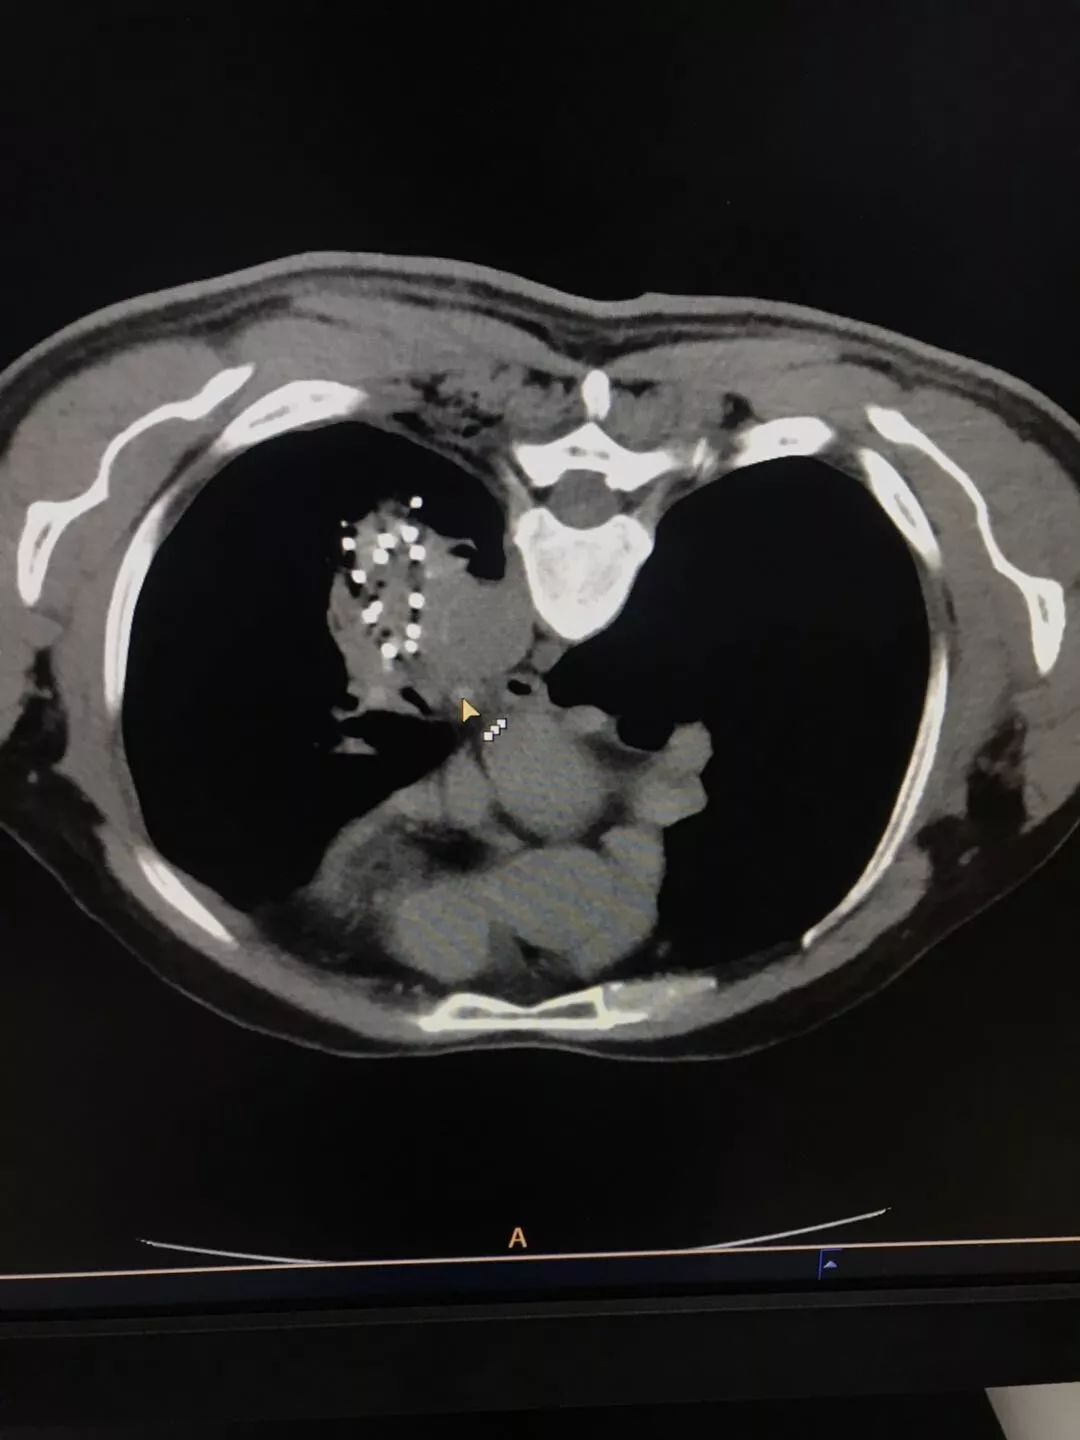

经过完善的术前检查,患者无明显125-碘粒子植入手术禁忌症,使用体部125-碘粒子植入计划系统进行术前计划,确定体部模板位置、角度,确定进针位置、125-碘粒子分布位置;术中使用定位模板,在CT引导下,精准地将9根穿刺针,按照术前计划穿入肿瘤。经CT验证后,使用125-碘粒子植入枪将125-碘粒子,共植入粒子55粒,按照术前计划完美地植入肿瘤中。

按术前计划植入粒子成功